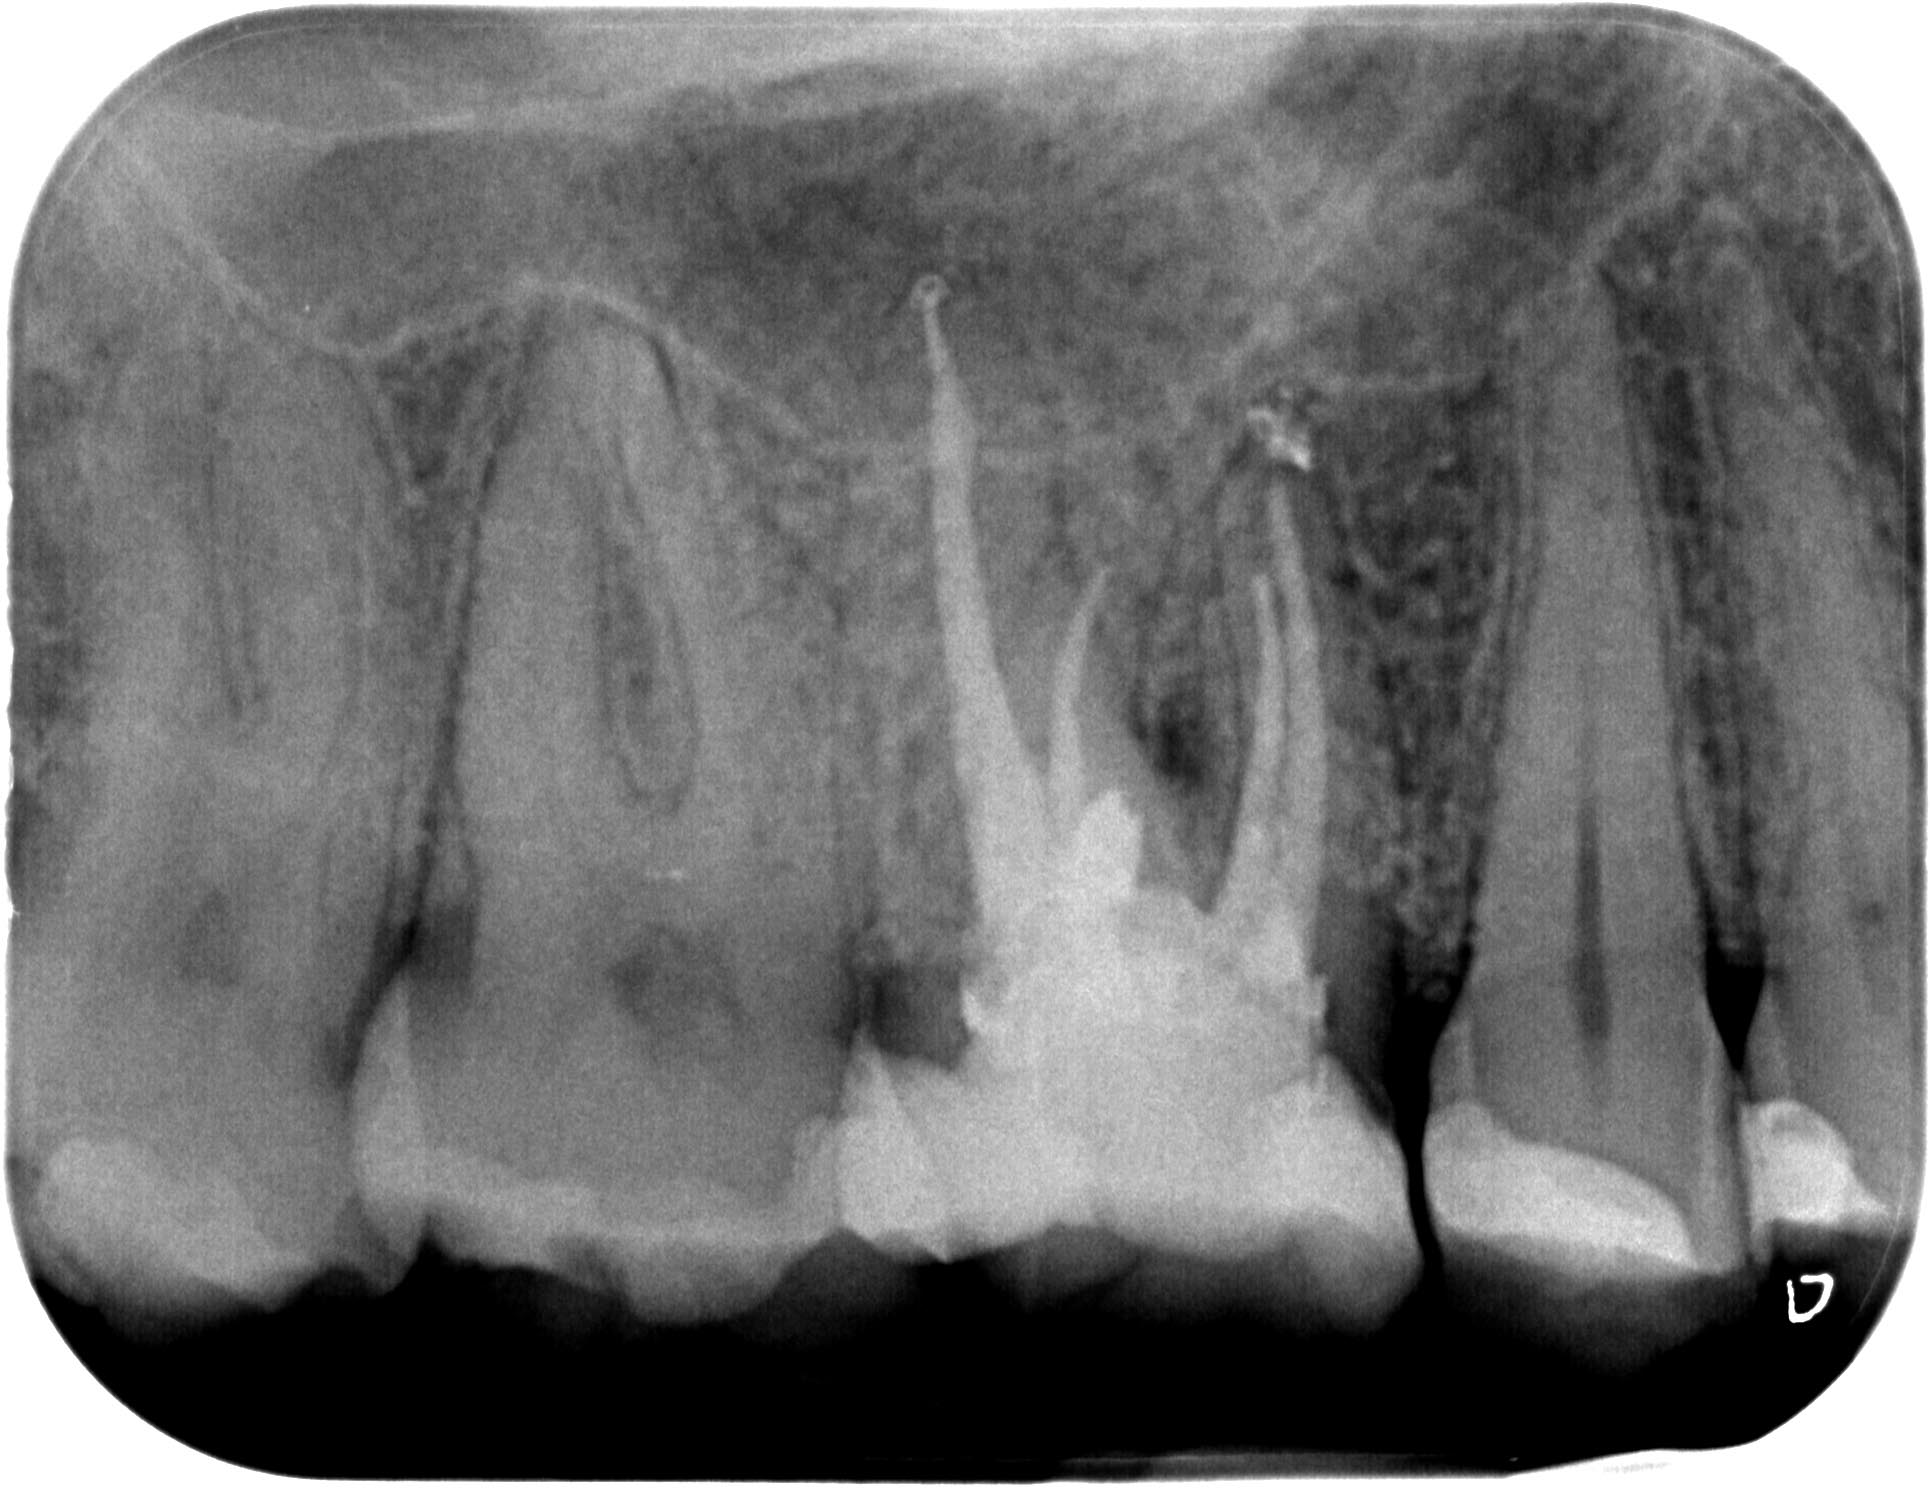

Unauffälliges Röntgenbild (Teil 2)